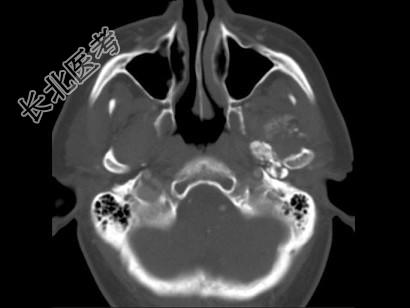

- 多项选择题男,60岁, 张口受限半年,CT检查如图所示, 正确的描述或诊断是 ( )

A、左侧颞颌关节周围软组织内见较多致密钙化影

B、左侧颞颌关节软组织未见肿胀

C、左侧颞颌关节面(颞骨面)骨质增生明显

D、左侧颞颌关节滑膜骨软骨瘤病

E、颞颌关节功能紊乱